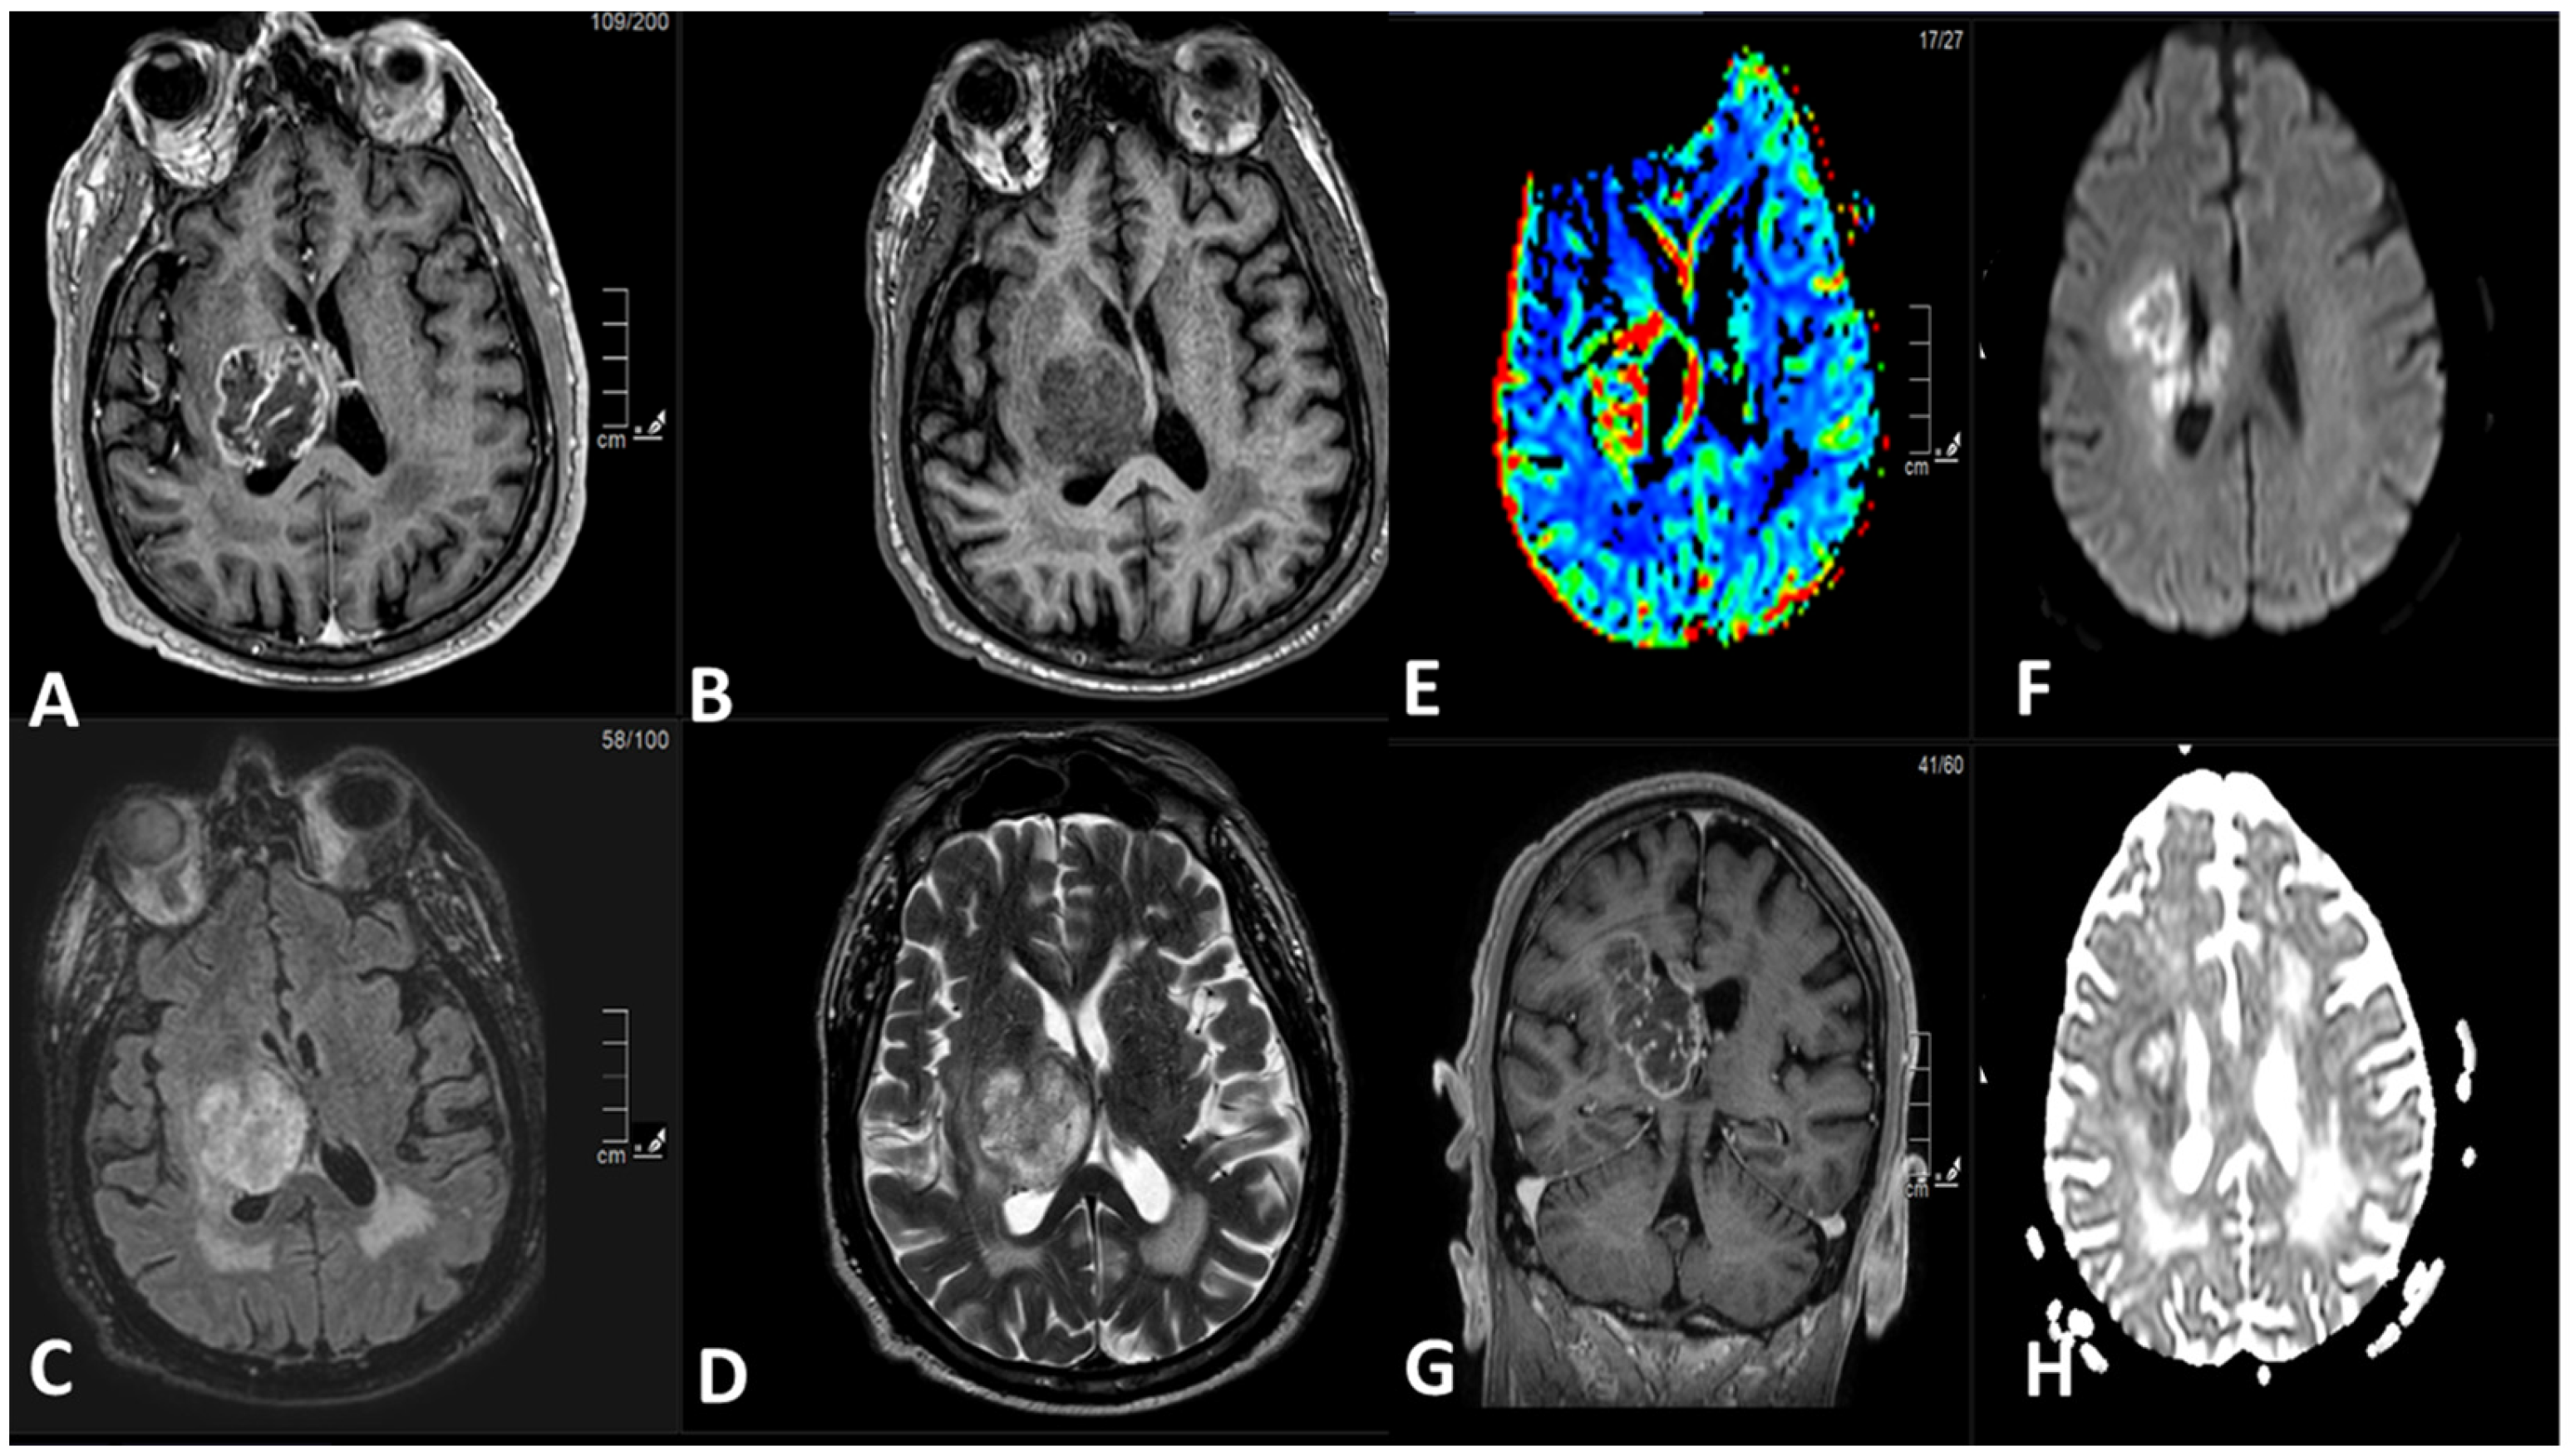

Figure 2 demonstrates an example of an intra-axial mass lesion in the right thalamus. It shows an irregular border, hypointense signal on T1-weighted sequence, heterogeneous signal on T2-weighted sequence with intermediate and hyperintense signal areas, and hyperintense FLAIR signal. The lesion shows peripheral irregular contrast enhancement with a rim of diffusion restriction and hyperperfusion. It results in a mass effect upon the body and trigone of the right lateral ventricle. There is very mild perilesional edema. The confluent T2, FLAIR hyperintense white matter signal in periventricular regions correlates most with sequelae of microvascular ischemic change. The coronal images show the craniocaudal extent of the lesion; there is a mass effect upon the ventricular system with a small tumor component within the corpus callosum.

Figure 2.

(A) Axial T1-weighted post IV contrast sequence. (B) Axial T1-weighted pre-IV contrast sequence. (C) Axial FLAIR sequence. (D) Axial T2-weighted sequence. (E) Dynamic susceptibility contrast (DSC) MR perfusion images, cerebral blood volume (CBV). (F) Diffusion weighted images (DWI), b 1000. (G) Coronal T1-weighted post IV contrast sequence. (H) Apparent diffusion coefficient (ADC) map.